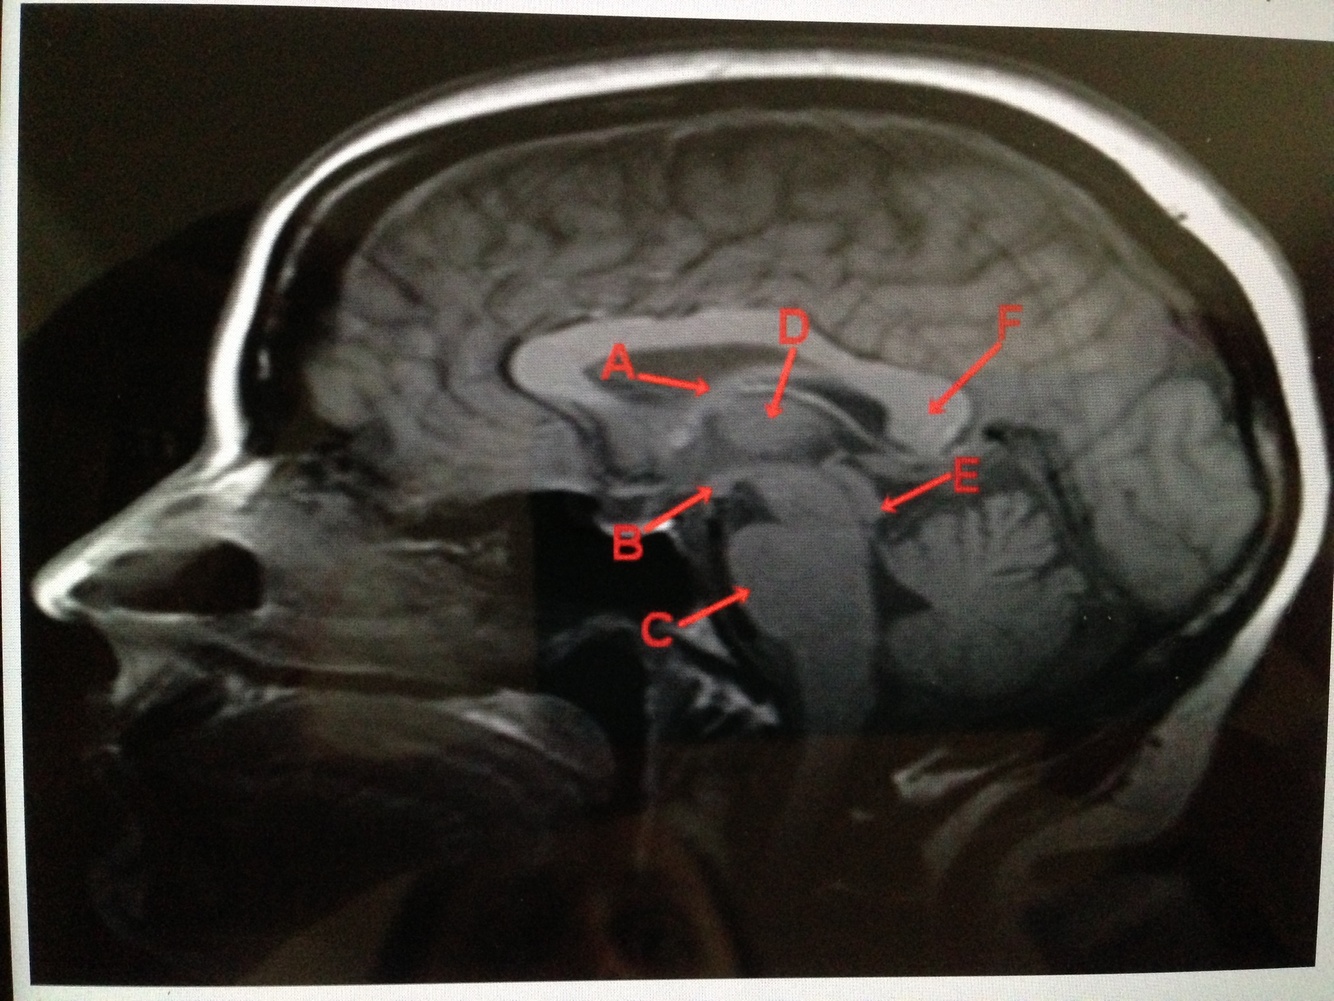

Man with short term memory loss, nystagmus, ophthalamoplegia & ataxia who’s breath smells like alcohol….. which of the structures is most likely damaged in this man’s brain?

B- the mammillary bodies –> he is experiencing Wernicke Encephalopathy and could progress to Korsakoff psychosis

CSF flows from the lateral ventricles to the 3rd ventricle via __________________ and then to the 4th ventricle via the _______________ and then out of the 4th and into the subarachnoid space through the __________ & __________

interventricular foramina of Monroe , cerebral aquaduct , lateral foramina of Luschka (2) or the medial foramin of Magendie